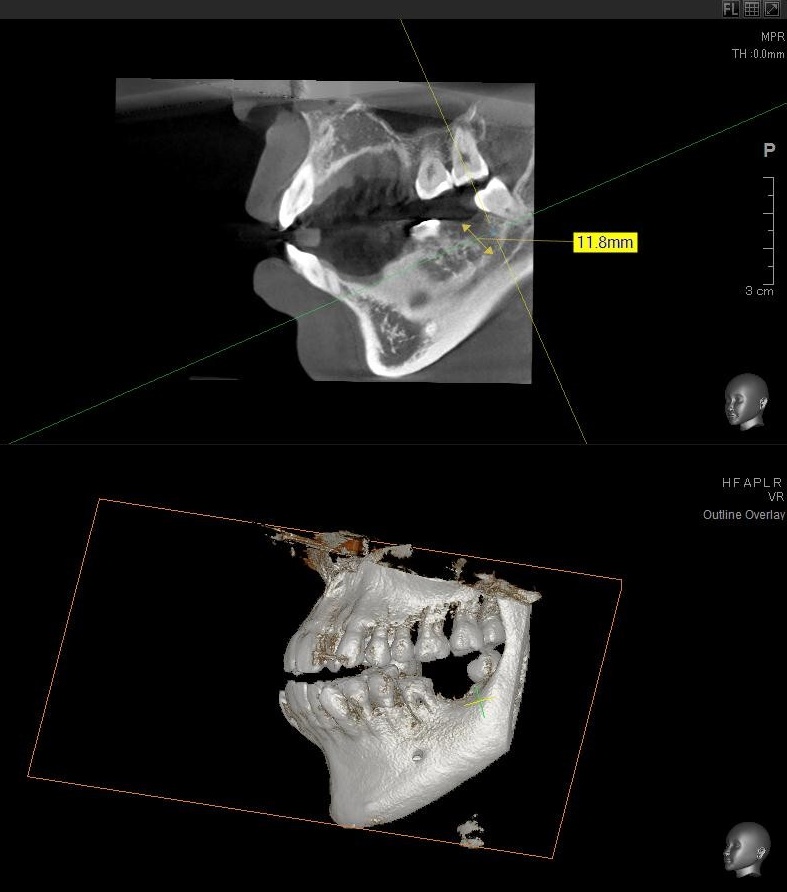

今回の患者様はインプラント植立を希望され、左下7番目の植立が決まりました。